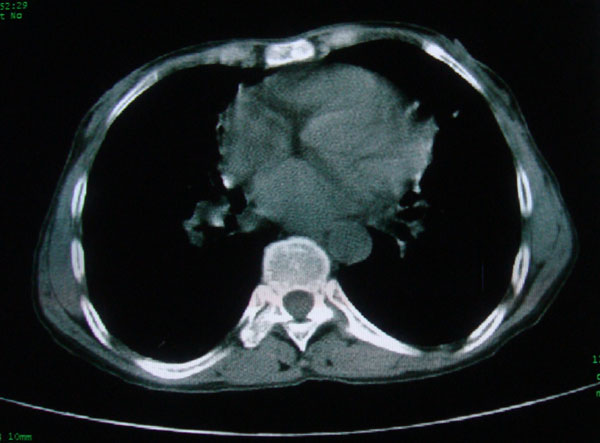

标题: CT15046:F59Y,咳嗽间断咳血丝痰就诊. [打印本页]

标题: CT15046:F59Y,咳嗽间断咳血丝痰就诊.

咳嗽\间断咳血丝痰就诊.

考虑支气管扩张并感染

1慢支伴感染;右下肺周围型肺癌。

本例应该是“慢性疾病并发多种合并症”即:慢支并感染并支气管扩张征!结合病灶分布 形态分析,不除外合并“继发性肺结核”!

慢性支气管炎伴全小型肺气肿、支气管扩张、感染、间质纤维化。

多考虑支气管扩张并感染,双下肺继发性肺结核不除外